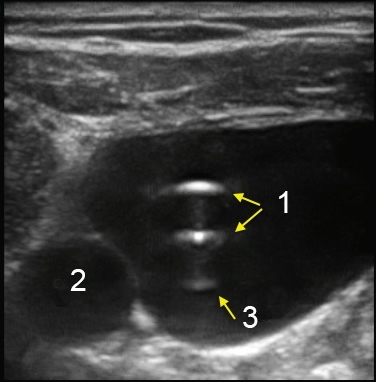

M-Turbo: Catheter in IJV Short Axis Image

Catheter

Carotid Artery

Artifact